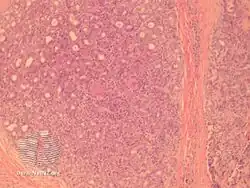

Aggressive digital papillary adenocarcinoma

Aggressive digital papillary adenocarcinoma is a cutaneous condition characterized by an aggressive malignancy involving the digit between the nailbed and the distal interphalangeal joint spaces.[1]:โ670โ

Aggressive digital papillary adenocarcinoma-pathology